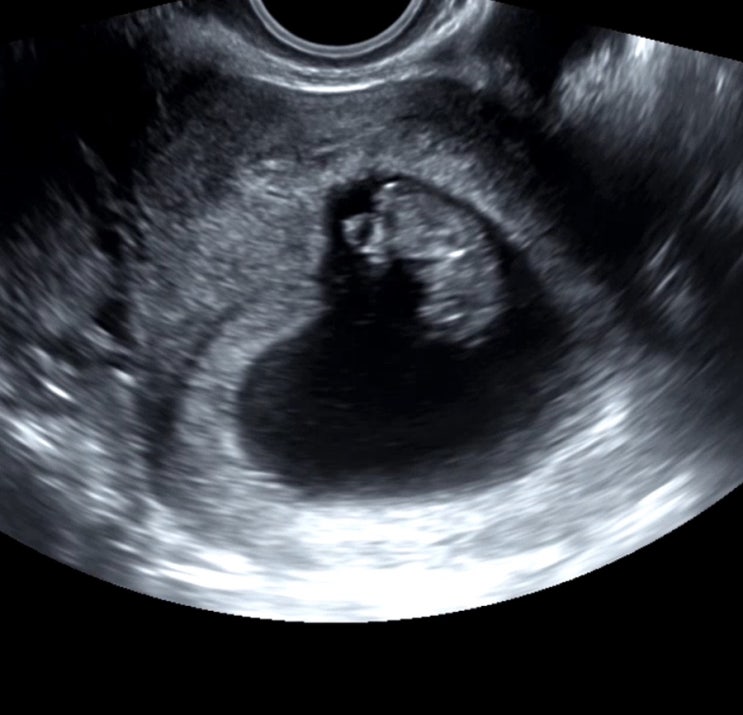

[예비맘 임신일기] 21주차 예비맘의 일상들(임밍아웃 두둥)

여러분 안녕하세요, 제가 오랜만에 돌아왔습니다. 마지막 글이 올해 3월이군요,, 3월 이후로 저는 아주 바...